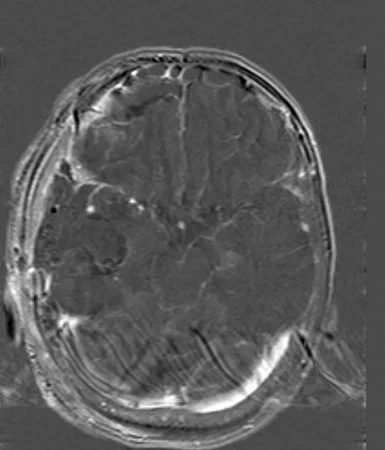

Η μετεγχειρητική μαγνητική τομογραφία εγκεφάλου (substraction sequences) δείχνει πλήρη αφαίρεση της βλάβης. Η ιστολογική εξέταση ανέδειξε γλοιοβλάστωμα (IDH1/2 mutant, MGMT neg).